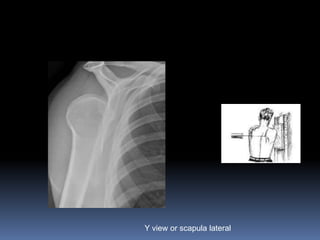

AP shoulder

Y view or scapula lateral

Internally rotated humerus giving light

bulb appearance. Y view showing

Posterior dislocation

posterior

dislocation.